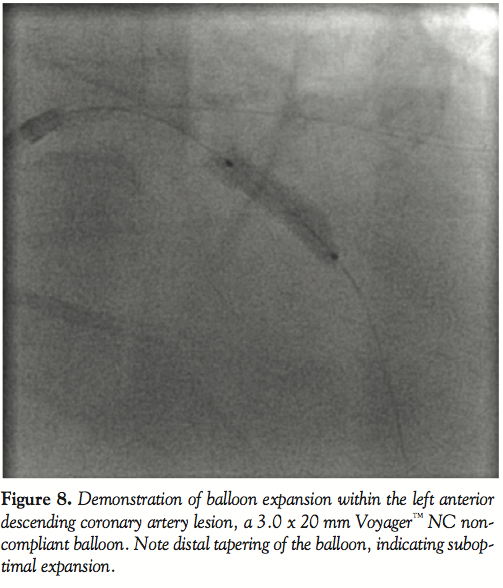

On day 3, the patient was brought back to the cath lab for staged PCI. An 8 French (Fr) Amplatz™ Left (AL) 2.0 guide (Boston Scientific, Natick, Massachusetts) was selected for increased support, and a Whisper™ wire (Abbott Vascular, Abbott Park, Illinois) was advanced easily through the lesion. Due to the lesion proximity to a large ramus intermedius bifurcation, a BMW™ wire (Abbott Vascular) was placed in the ramus for protection from potential plaque shift. A 3.0 x 20 mm Voyager™ NC noncompliant balloon (Abbott Vascular) was used for predilation, inflated at 14 atm for 30 seconds, to apparent full expansion. A Cypher sirolimus-eluting stent (on Bx Velocity™ platform [Cordis Corporation, Miami Lakes, Florida) was requested, but was not stocked in the 3.5 x 23 mm size that was required. Thus, a 4.0 x 24 mm Taxus paclitaxel-eluting stent (on Liberte™ platform [Boston Scientfic]) was chosen, deployed at 16 atm for 30 seconds. Postdeployment cineangiography appeared to demonstrate full expansion of the stent within the target stenosis (Figure 3A). However, when attempts were then made to withdraw the balloon into the guide, it would not disengage from the stent scaffolding.

Of course, the extensive calcification in this particular case placed the patient at higher risk for complications overall; in fact, calcification of a lesion has been shown to be one of the most significant predictors of procedural failure in PCI.17 Retrospectively, perhaps more consideration could have been given to planned CABG, or the use of adjunctive techniques such as rotational atherectomy. Though the latter has fallen out of favor in recent years as a stand-alone technique, many reports have shown high procedural success when used for debulking of plaque prior to stenting (the so called Rota-stent technique) in heavily calcified lesions, achieving an impressive 89–98% procedural success.18 It also may be of particular utility for lesions in which the PCI balloon does not fully expand.19On careful review of the predilation image, this occurred to some extent at the distal tip of our balloon (Figure 8).